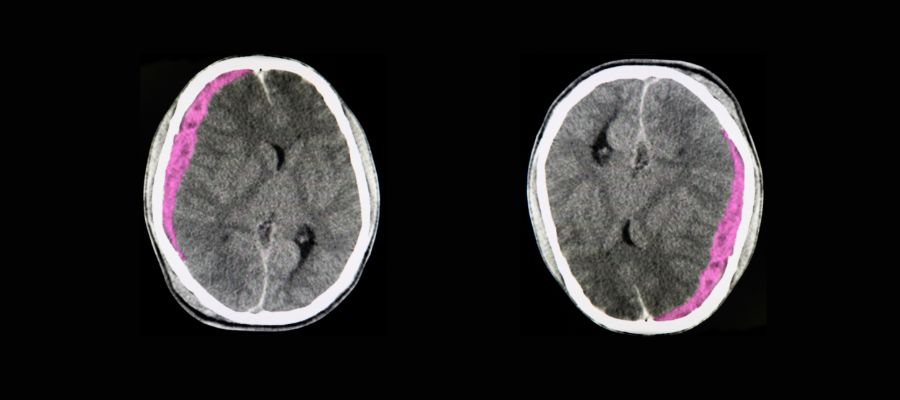

hematome sous dural

L'hématome sous-dural représente la complication la plus fréquente et la plus redoutable chez les seniors. Cette accumulation de sang entre le cerveau et la dure-mère peut se développer lentement, sur plusieurs jours ou semaines. Chez les personnes âgées, même un choc mineur peut provoquer cette lésion en raison de la fragilité accrue des vaisseaux sanguins et de l'atrophie cérébrale naturelle qui crée un espace plus important dans la boîte crânienne. Les symptômes peuvent inclure des maux de tête persistants, une somnolence progressive, des troubles de la mémoire ou des changements de comportement.